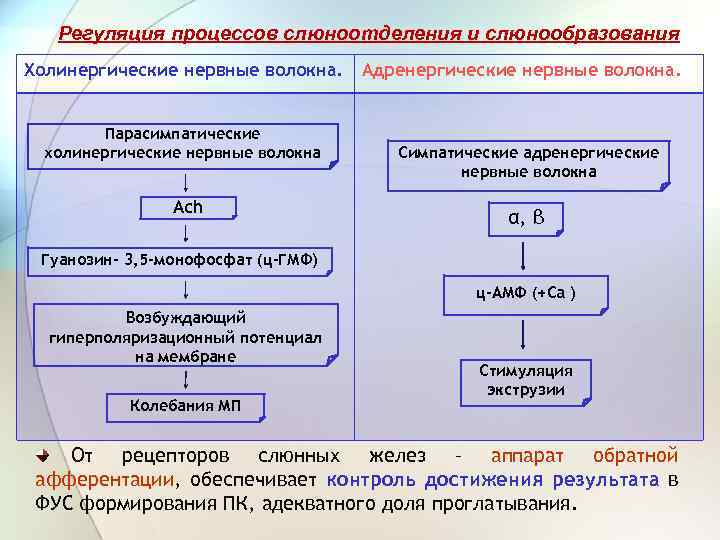

Регуляция процессов слюноотделения и слюнообразования Холинергические нервные Адренергические нервные волокна. Возбуждение этих волокон вызывает выделение Аch и выделяется большое количество жидкой слюны, содержащей много солей и мало органических веществ. Такая слюна выделяется в ответ на попадание в полость рта некачественных, непригодных пищевых веществ или инородных тел => «отмывная слюна» . Преганглионарные волокна отходят от нейронов слюноотделительных ядер МО через вегетативные ганглии – постганглионарные волокна иннервируют слюнные железы. Парасимпатические влияния всегда сильнее симпатических. Их раздражение сопровождается высвобождением норадреналина и приводит к выделению небольшого количества слюны, богатой органическими веществами с малым содержанием солей. Преганглионарные волокна отходят от боковых рогов II - VI грудных сегментов спинного мозга и заканчиваются в верхнем шейном ганглии; отсюда постганглионарные н. в идут через plexus caroticus internus и достигают околоушной слюнной железы, а через plexus caroticus еxternus подъязычной и поднижнечелюстной железе.

Регуляция процессов слюноотделения и слюнообразования Холинергические нервные волокна. Парасимпатические холинергические нервные волокна Ach Адренергические нервные волокна. Симпатические адренергические нервные волокна α, β Гуанозин- 3, 5 -монофосфат (ц-ГМФ) ц-АМФ (+Ca ) Возбуждающий гиперполяризационный потенциал на мембране Колебания МП Стимуляция экструзии От рецепторов слюнных желез – аппарат обратной афферентации, обеспечивает контроль достижения результата в ФУС формирования ПК, адекватного доля проглатывания.